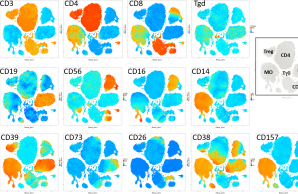

Project 7: Exploring the cross-talk between bone and the immune system in early-onset low BMD disorders

A comprehensive profiling of the immune system across patients with early-onset low BMD has not been performed. In P7 we want to explore the contribution of disturbances in immunity to early-onset low BMD, and also the impact of bone-related gene defects and of bone disease-specific treatment on immune cell function.